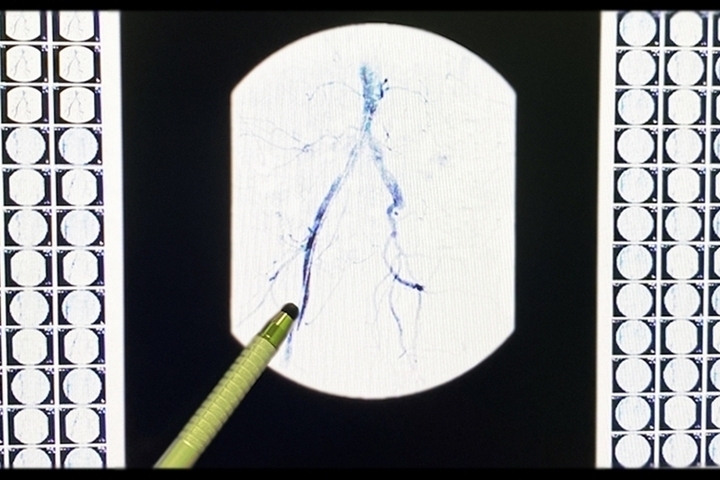

Фото: Рязанская областная клиническая больница

Врачи Рязанской областной клинической больницы провели операцию 51-летнему пациенту с инфарктом миокарда. Об этом сообщили в пресс-службе медучреждения.

В ходе лечения врачи выполнили коронарную ангиографию для оценки состояния сосудов, так как ситуация осложнялась увеличенным диаметром артерии.